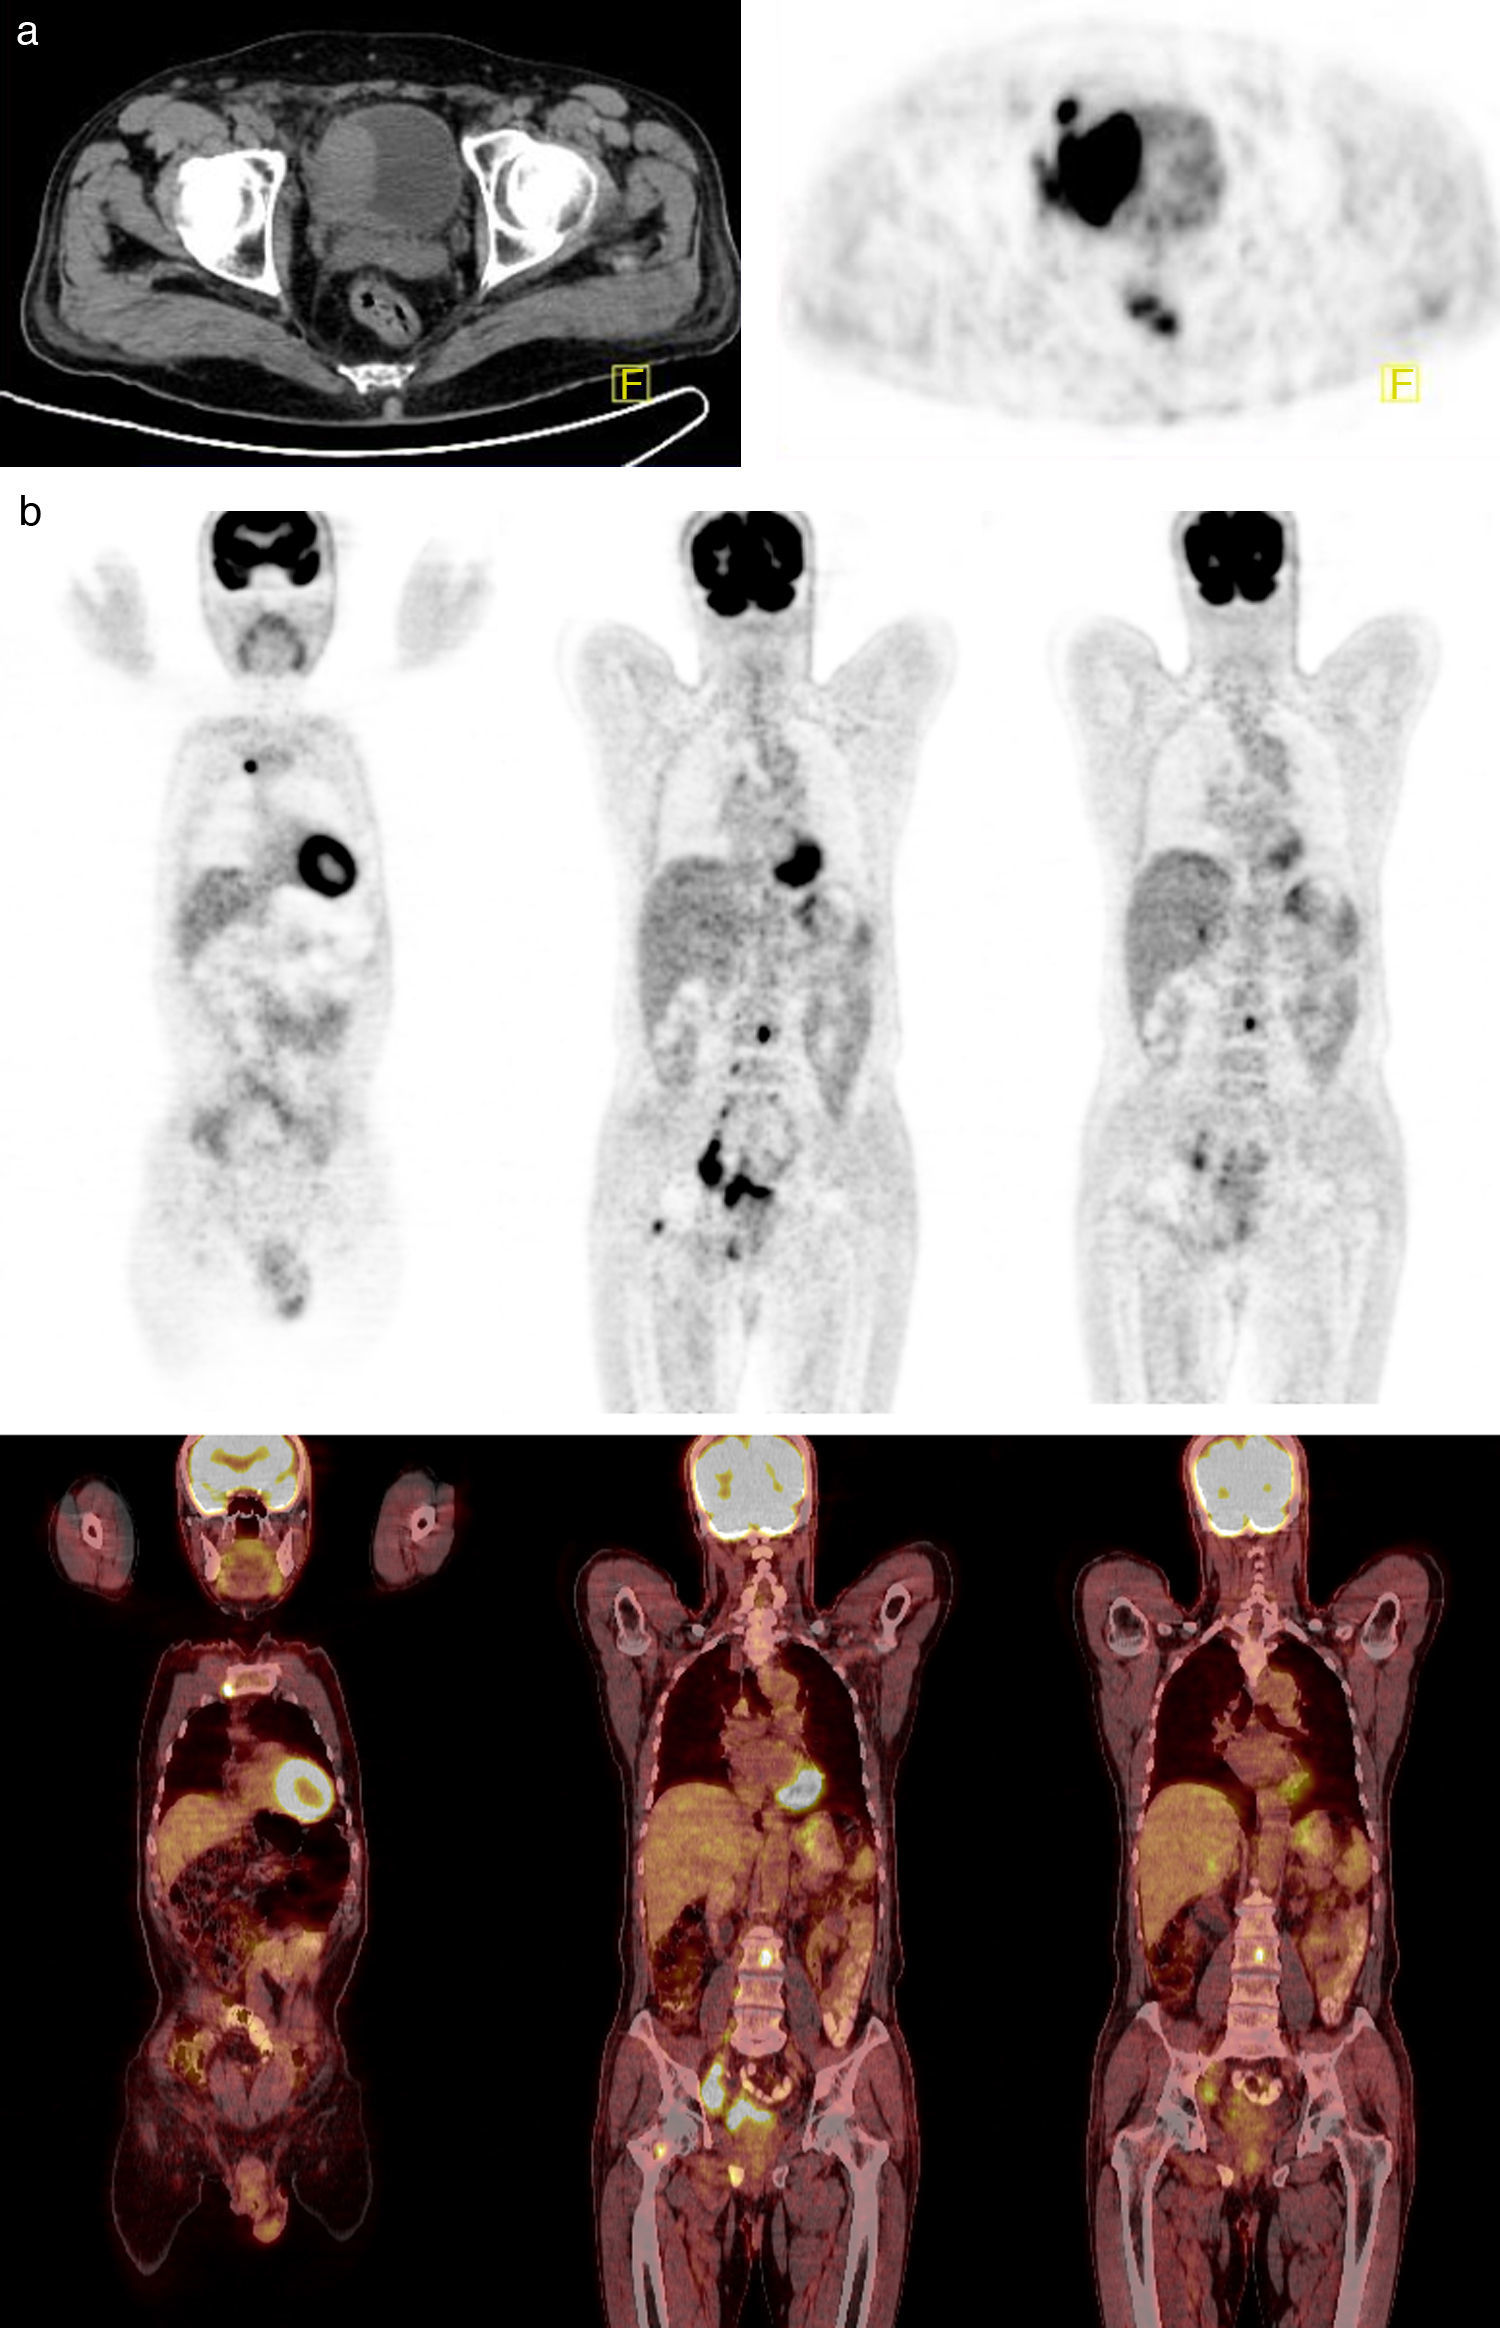

18F-FDG PET has been regarded as a limited value in urooncology due to urinary excretion of the tracer. The purpose of this retrospective study was to investigate the clinical value of dual-phase FDG PET/CT with forced diuresis protocol (iv furosemide-voiding and oral hydration) in invasive or high grade bladder cancer.

MethodsFifty-one patients were included in this study. All patients underwent standard staging procedures and dual-phase FDG PET/CT before planned therapy. PET/CT findings before and after furosemide were compared with each other for pelvic region. Dual phase PET/CT findings were also compared with the results of prior imaging studies and all findings were correlated with final diagnosis (histopathology or clinical follow-up for at least 12 months).

ResultsIntravesical FDG activity significantly decreased in 90% of the patients with forced diuresis protocol. Eighty eight percent of the bladder findings and 20% of the local lymph node metastases, and other pelvic findings (local invasion and second primary malignancy of prostate) were detected only by the additional pelvic PET/CT images. As a result, dual phase PET/CT changed the staging and/or the therapy strategy in 16 patients (31%).

ConclusionDual phase FDG PET/CT contributes staging and decision of therapy strategy by detecting local disease and pelvic metastases with high accuracy when combined with forced diuresis protocol. Thus, we recommend dual phase imaging method with forced diuresis protocol in FDG PET/CT for bladder cancer and all other urogenital system malignities.